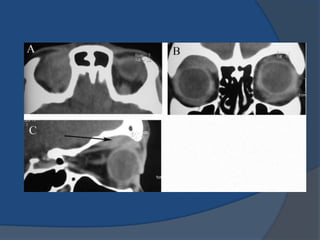

Orbital pseudotumor:

 CT imaging:

 Focal & infiltrative.

 Poorly circuscribed.

 Mass or thickening on

muscle, lacrimal and

orbital structures.

 Moderate diffuse

enhancement.

 Increase attenuation

on late enhancing

phase.

Orbital pseudotumor:  CTimaging:  Focal & infiltrative.  Poorly circuscribed.  Mass or thickening on muscle, lacrimal and orbital structures.  Moderate diffuse enhancement.  Increase attenuation on late enhancing phase.